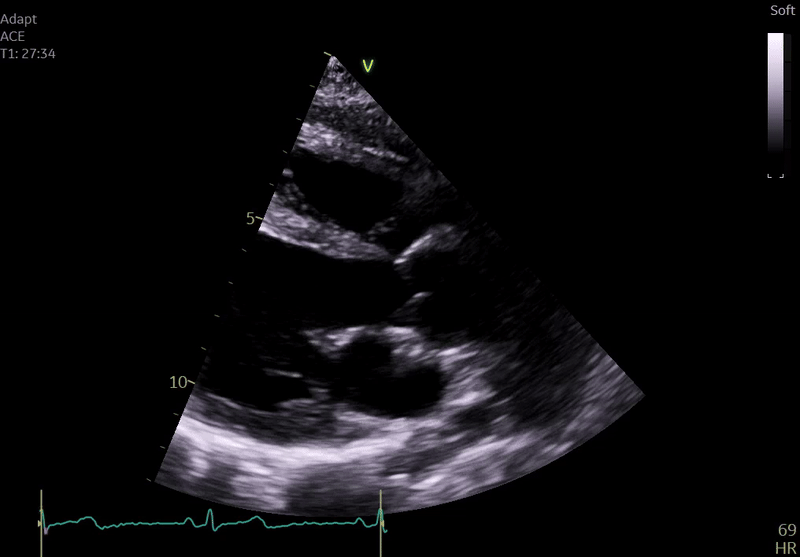

Echocardiography on admission:

Transthoracic Echocardiography on Admission

• Mildly dilated left ventricle (LVEDD 55 mm)

• Severe global hypokinesis

• Left ventricular ejection fraction 20–25%

• Mild mitral regurgitation

• Right ventricle normal in size and systolic function